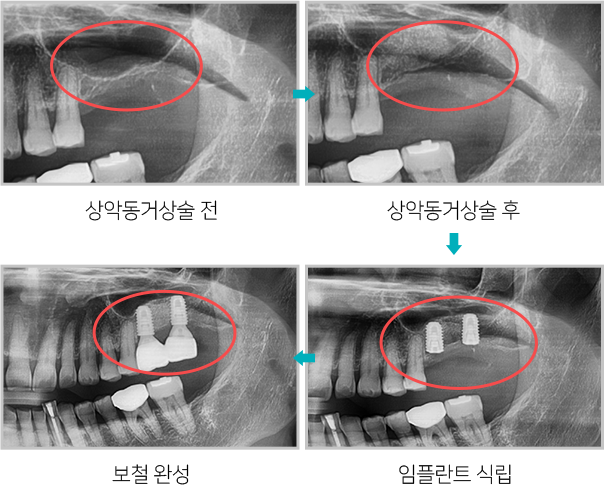

상악동거상술 전후

상악동거상술 모식도

위턱뼈 속의 비어있는 공간을 상악동이라고 하는데

상악동과 잇몸뼈 사이에 임플란트를

심을 수 있는 만큼의

뼈가 남지 않았을 때, 잇몸뼈 위쪽에 위치한 상악동의

아래벽을 위쪽으로

들어올리고 그 공간에 뼈를 채워

넣어서 임플란트를 심을 수 있는 뼈의 양을

확보하는 술식입니다.